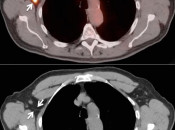

Partial Volume Effects:

When the activity of a specific volume of tissue is being measured, the actual measurement includes adjacent tissues, falsely influencing (usually decreasing) the SUV calculation.

This effect results from the intrinsic poor resolution of PET scanning, and is influenced by the imaging parameters of the machine, the size and morphology of the object being evaluated, and the distribution of FDG in the body.

Partial volume effects occur for nearly all lesions less than 3.0 cm in diameter. The smaller the lesion, the more significant the partial volume effects.

The effects are so significant for small lesions, that lesions less than 8.0-mm should be considered “beneath the resolution of PET”.  [FIG. 4]